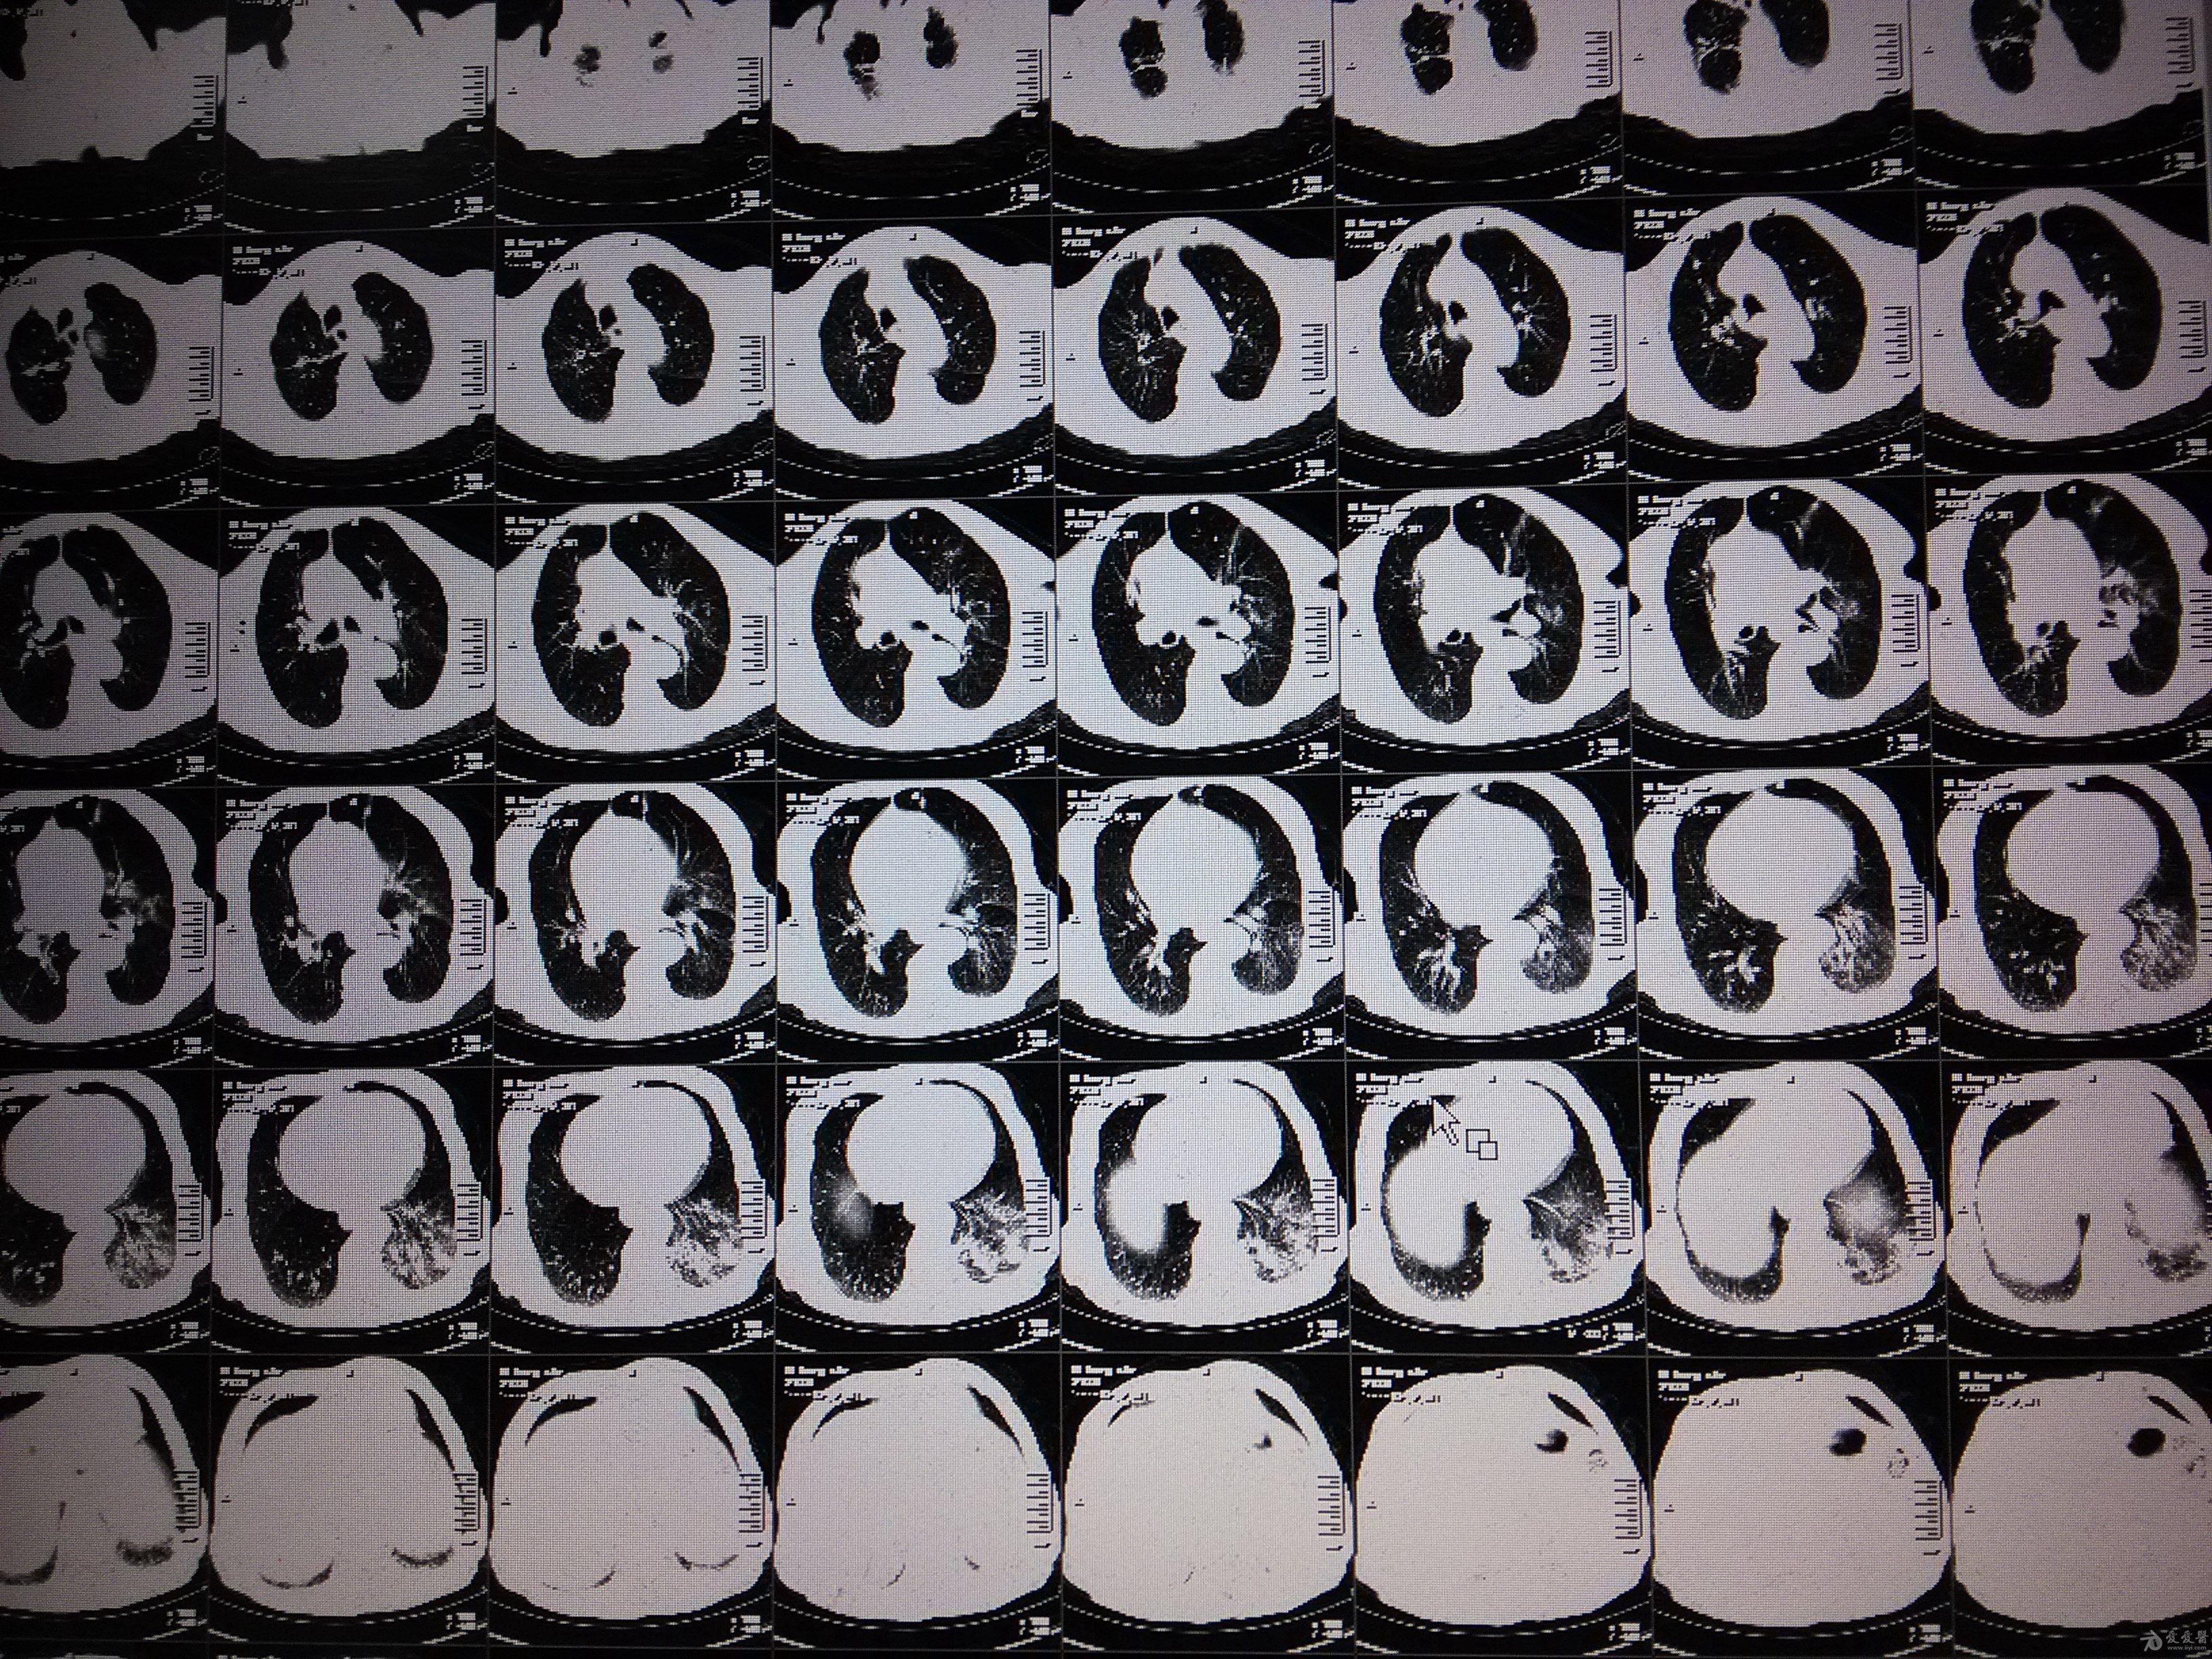

图片尺寸1440x1080

35分胸部ct显示双肺下叶阴影,坠积性肺炎

图片尺寸1000x1334